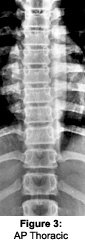

The routine thoracic spine study includes the following: AP and lateral thoracic spine views. The AP thoracic view is taken with a grid technique, using a 7 x 17 or 14 x 17, at 40" film focal distance and a kVp of 76-80, with a time commensurate with patient's thickness. Collimation is a little less than the 7 x 17 cassette. If possible, filter the top 1/3 of the film or use the anode heel effect. Central ray is about the level of T6. X-ray is done on inspiration.